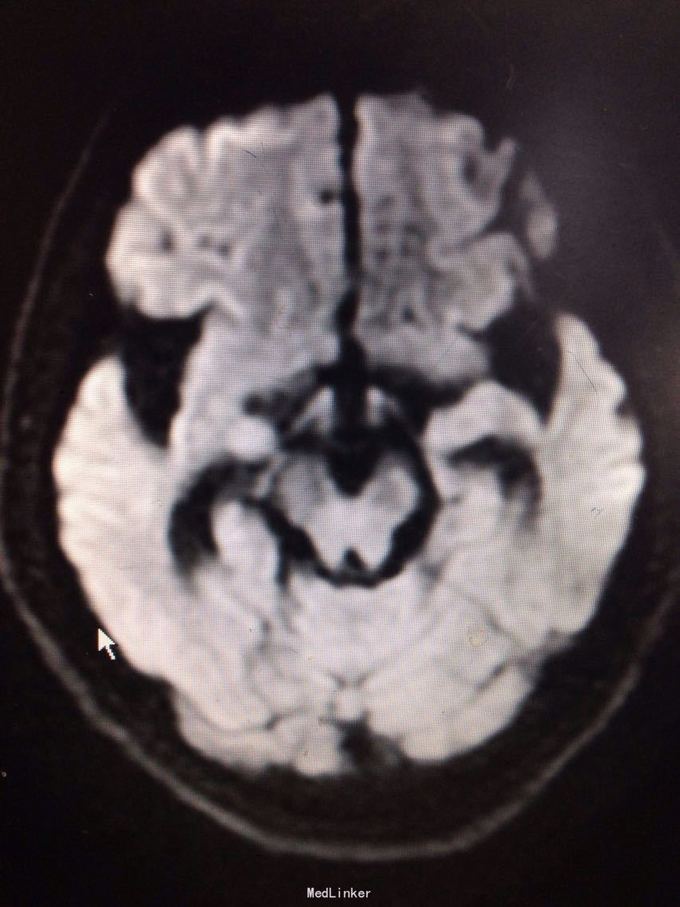

查体可见右手3、4、5指肌力3级,余肢体肌力5级。四肢腱反射减弱。 颅脑MR提示:右侧中央前回皮层下亚急性腔梗,脑萎缩,脑白质变性。 糖化血红蛋白8.2%。